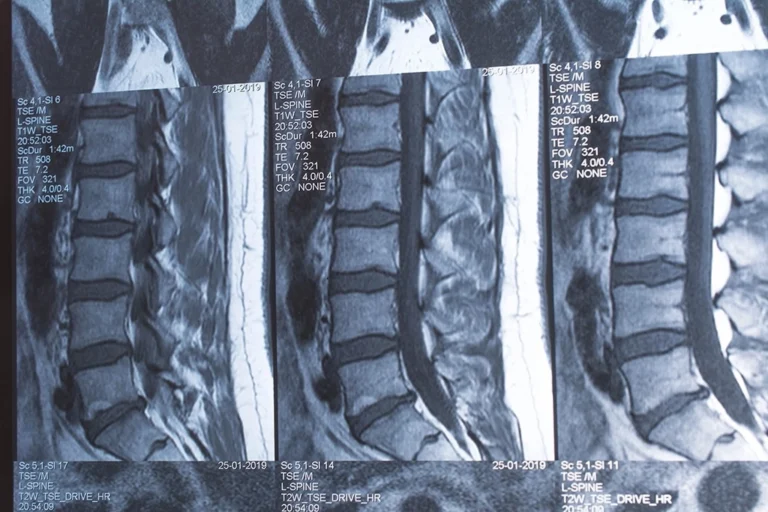

So, your doctor recommended a back MRI. Getting a back MRI can come with a lot of unknowns from how to prepare to why your doctor ordered this scan, but keep reading to find the answers to your questions and the peace of mind you need. MRIs use magnets to produce detailed scans of your soft tissues and internal organs, nerves, and bones.

Because of their high clarity and ability to take quality scans of soft tissue, a back MRI can be helpful in diagnosing or monitoring any of the following issues:

- Slipped or herniated lumbar discs

- Abnormalities in the vertebrae or spinal cord

A back MRI is a diagnostic imaging technique that uses magnets to produce detailed scans of the soft tissues, internal organs, nerves, and bones in your back. It is especially useful in diagnosing spinal issues and causes of lower back pain.